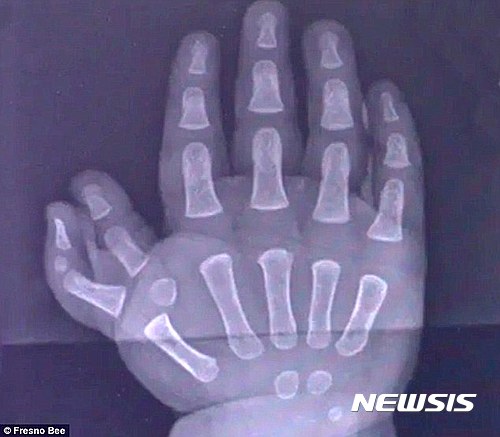

【서울=뉴시스】엄지손가락이 2개인 카터의 오른손 엑스레이(X-Ray) 사진. (사진출처: 데일리메일) 2017.03.10.

9일(현지시간) 영국 일간 데일리메일에 의하면, 미국 캘리포니아 프레즈노에 사는 '키리에 카터'라는 이름의 이 아기는 다지증(多指症)으로 오른손에 엄지손가락이 2개, 왼손에 3개를 가지고 태어났다. 다지증은 정상인보다 손·발가락을 많이 갖고 태어나는 희귀성 질환이다.

카터는 지난해 8월 왼손의 엄지손가락 3개 중 2개를 제거하는 수술을 성공적으로 받았으며, 지난달 16일 오른손 엄지손가락 2개 중 1개의 제거 수술도 성공적으로 마쳤다. 카터는 오른손 엄지와 검지 사이에 엄지손가락 하나가 더 있었는데, 의료진들은 이 엄지를 제거하는 수술을 실시했다.